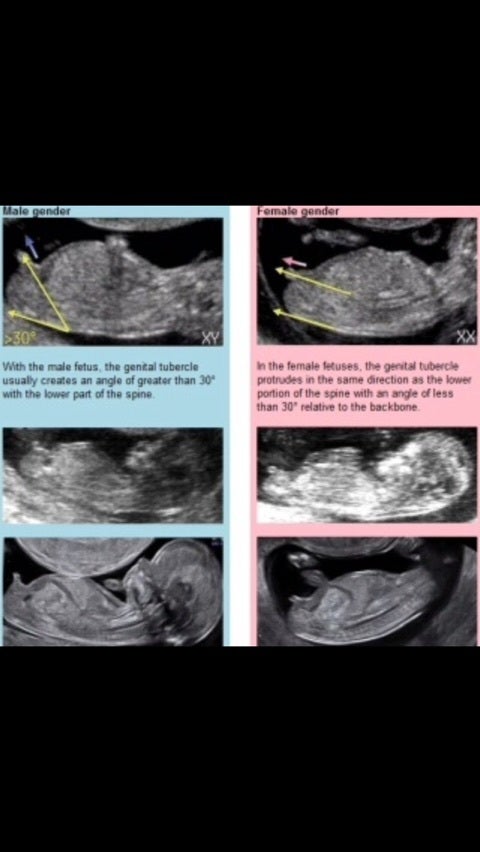

おなかの赤ちゃんは男 女 いつ どこを見てわかる

エコー写真を妊娠の経過別に紹介 見方や性別の見分け方

妊婦健診の楽しみ方 エコー写真から 性別 を見分ける方法 17年12月13日 ウーマンエキサイト 1 2

エコー写真を妊娠の経過別に紹介 見方や性別の見分け方

エコーの性別の見分け方 節約しながらも丁寧な暮らしを忘れずに

妊婦健診の楽しみ方 エコー写真から 性別 を見分ける方法 17年12月13日 ウーマンエキサイト 1 2

妊娠11 12 13週で性別が分かる Baby Nub ベビーナブ の見分け方を紹介

医療監修 エコー写真を妊娠の経過別に紹介 写真の見方や性別の見分け方 ママリ